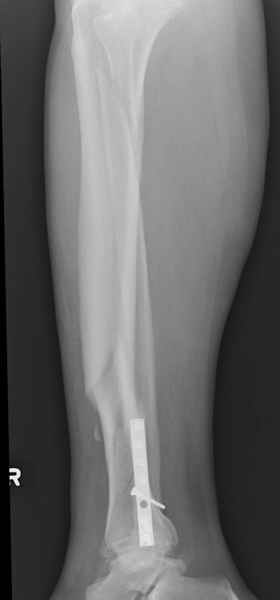

У меня молодой врач на линии, снимки отправил через эл. почту,

спрашивает что делать с больным который поступил недавно, фермер 55 лет падение при пьяной драке в баре, года два назад перенес операцию на лодыжке, на снимках и КТ перелом без вовлечения сустава,

Повреждение такой локализации, на которой применимы и аппарат (классический Илизарова или гибридный), пластина, особенно Locked Plate, и гвоздь с блокированием. В нашей клинике был бы выполнен закрытый интрамедуллярный остеосинтез. Желательно использовать гвоздь с возможностью провести более чем 2 обычных фронтальных винта в дистальном отломке.

Здесь мы использовали новый Synthes Nail с дополнительными дырками, в проксимальной части 4: по две косых и поперечные (один стандартный а другой динамический), в дистальной части две поперечные, прямая и косая. Вес больного более 120 кг, нагрузку начнем через месяц.

Получилось красиво, поздравляю. Вверху можно было ограничиться одним винтом во фронтальное статическое отверстие, зачем два 45-градусных?

При такий спирали задний край tibia может быть сломан - нет ли этого в данном случае? На всякий случай можно было ввести 1-2 винта 4,5 мм спереди назад мимо гвоздя. Хотя самый дистальный блокирующий винт, возможно, зацепил этот отломок. А какой тут диаметр гвоздя и locking винтов?